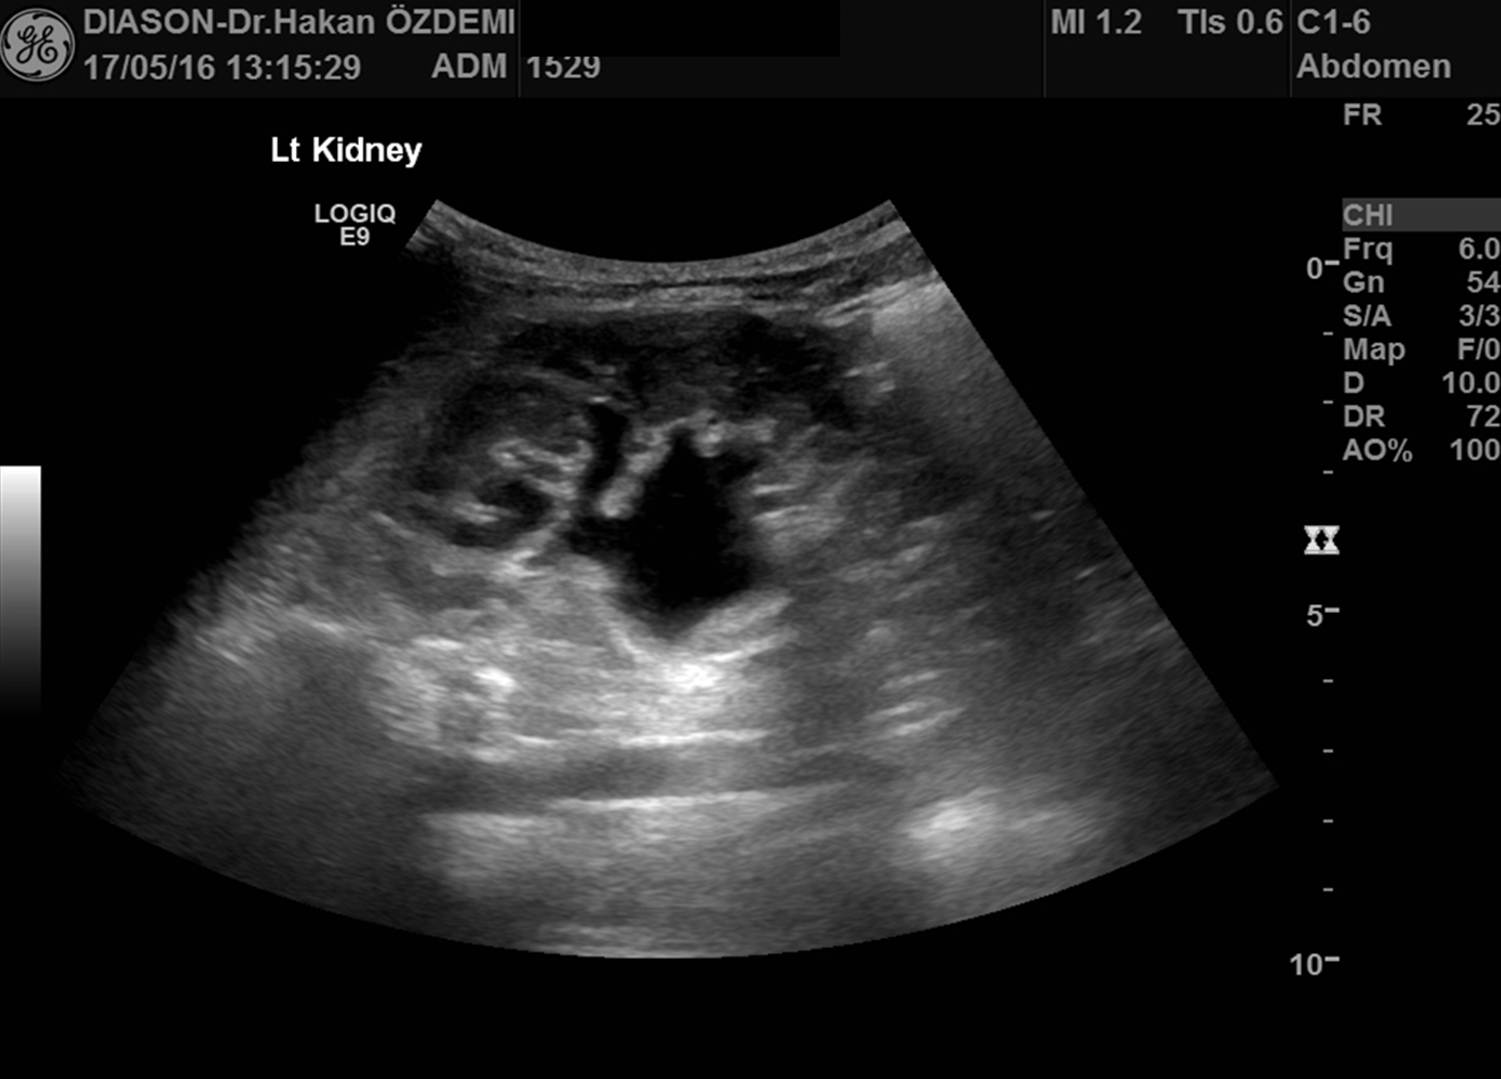

Ultrason, yüksek frekanslı ses dalgaları (ultrases) kullanılarak vücut içindeki organların ve diğer yapıların görüntülenmesi yöntemidir. Ultrasonda kullanılan ses dalgaları insan kulağının işitemeyeceği kadar yüksek frekansa sahiptir. Ultrason görüntülemede iyonizan radyasyon (X-ışınları) kullanılmadığı için bilinen zararlı etkisi bulunmamaktadır.

Ultrason cihazı, içerisinde bilgisayar ve elektronik aletlerin bulunduğu bir konsol, görüntülerin izlendiği bir ekran ve vücudu taramada kullanılan prob (transdüser) dan oluşmaktadır.

İnceleme sırasında prob ile vücut yüzeyi arasındaki temas jel aracılığı ile sağlanmaktadır. İncelenen bölgeye jel sürülmesinin nedenleri yüzeyin kayganlaştırılmasını sağlamak ve probun hava ile temasını önlemektir. Ultrason görüntülemenin temeli, yarasalar ve gemilerin kullandığı "sonar" ile aynıdır. Ses dalgaları vücuttan geçerken oluşan yansımalar, objenin uzaklığı, büyüklüğü, şekli ve yoğunluğunu tanımlamada kullanılır.

Ultrason probları, hem ses üreteci (hoparlör) hem de ses alıcısı (mikrofon) olarak çalışır. Prob cilde bastırıldığında vücut içine yüksek frekanslı, duyulamayan ses dalgaları yollar. Ses dalgaları vücuttaki doku ve sıvılardan yansıdıkça, prob yansıyan dalgaların özelliğini ve şiddetini kaydeder. Doppler ultrason da ise, prob ses dalgalarının yönü ve şiddetindeki küçük değişiklikleri kaydeder.

Bu yansımalar prob içinde bulunan özel kristaller aracılığıyla elektrik sinyallerine dönüştürülür. Daha sonra cihazın içinde yeralan bilgisayar aracılığı ile bu sinyallerden ekranda izlenen gerçek zamanlı görüntüler oluşturulur.